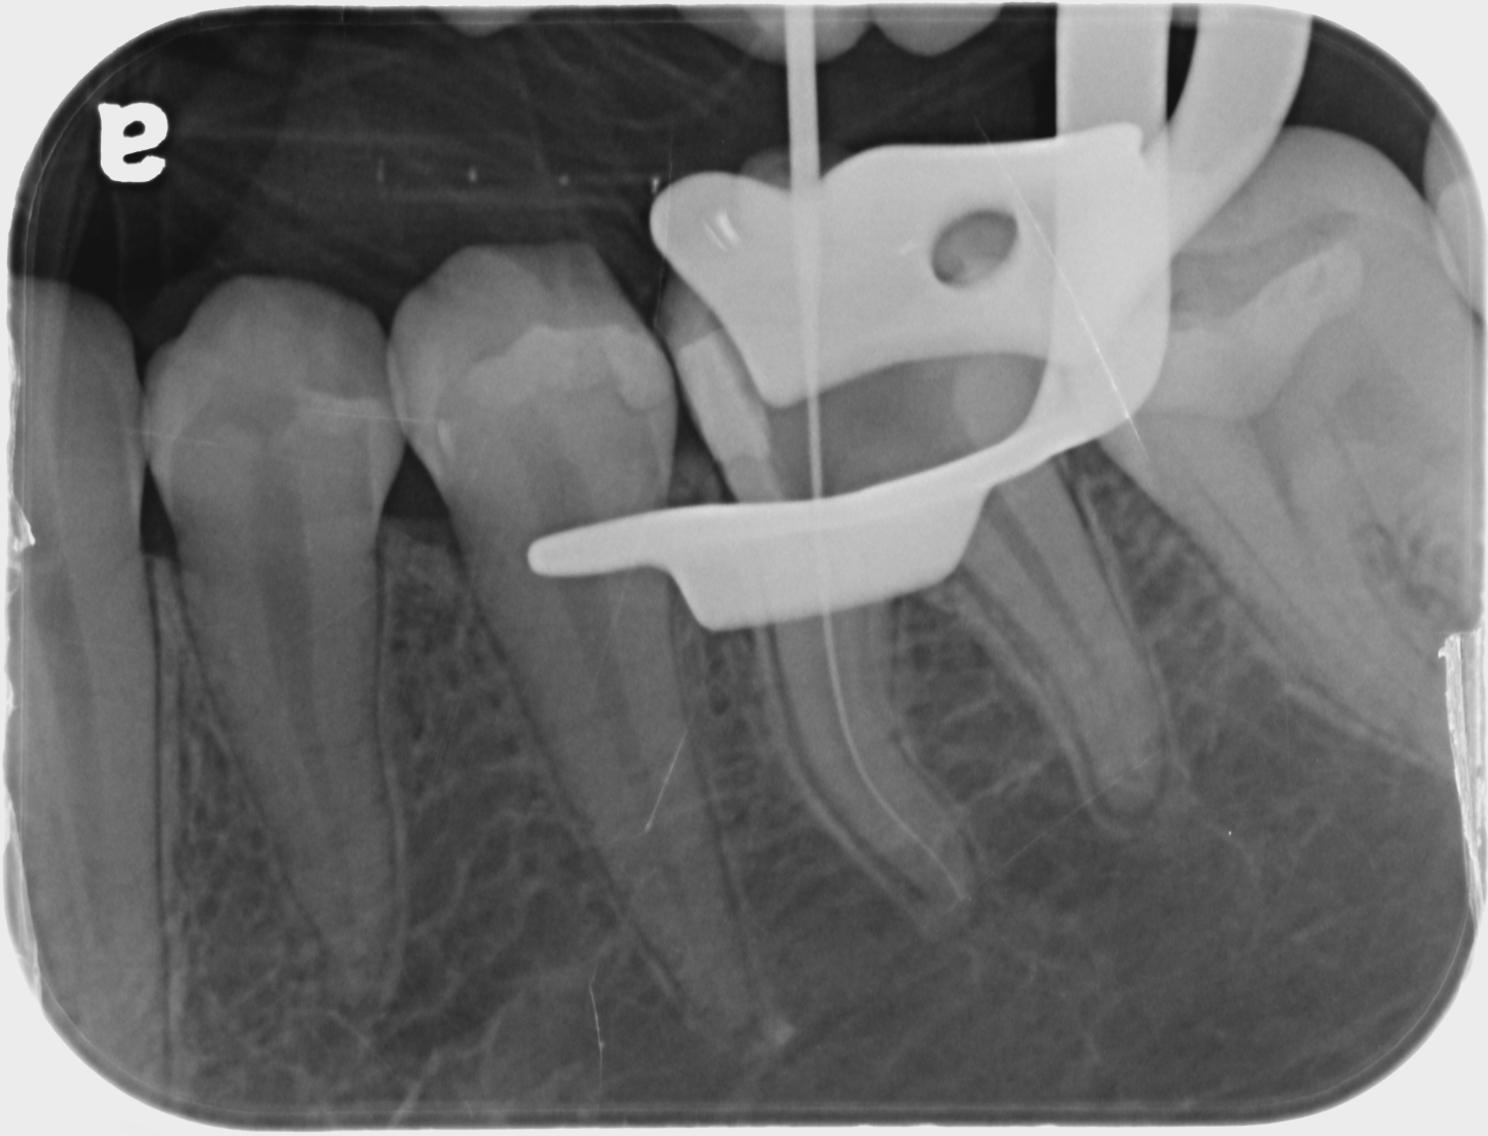

- Endodontic Radiology (Hands On)